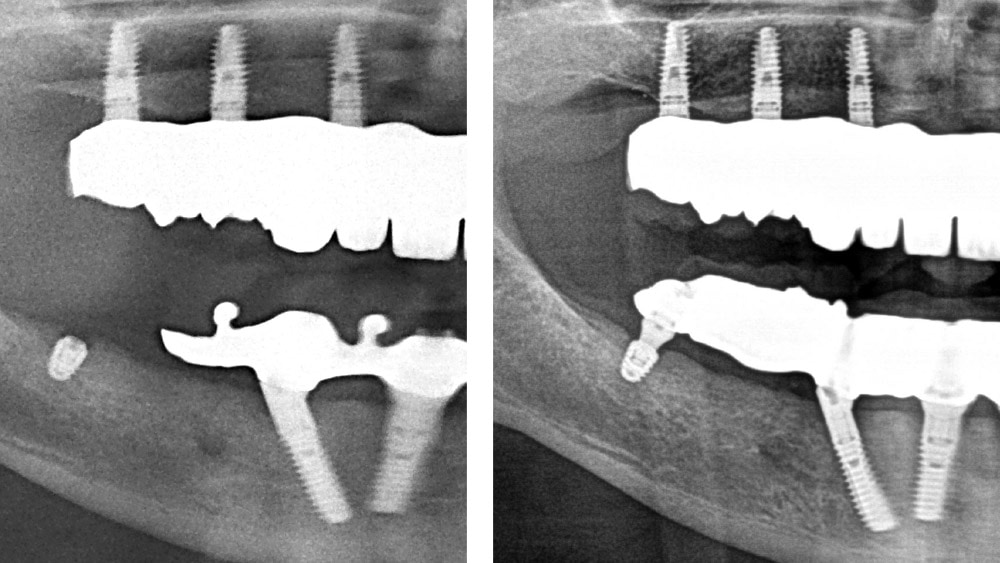

copaSKY köprü abutmentı, çekici olmayan bir abutmenttır. Düz konik bağlantı, iki implant arasında 20°’lik bir angulasyonun dengelenmesini sağlar. Bu nedenle çoğu köprü, diş laboratuvarında simante edilebilir.

Restorasyon kolayca birleştirilebilir ve oklüzal vidalarla sabitlenebilir. Uzun konik bağlantı, lateral ve oklüzal kuvvetleri doğrudan üst yapıdan implanta aktarmaktadır. Bu nedenle vida, gevşeme ve kırılmaya karşı korunur.